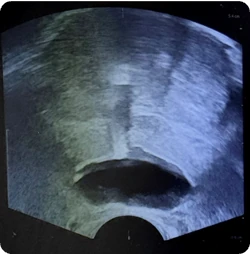

169 cc prostate ultrasound saggital view showing BioProtect Balloon Spacer, prostate, and rectum.

Saggital Ultrasound

Image courtesy of of Dr. Vishesh Agarwal, Radiation Oncologist.